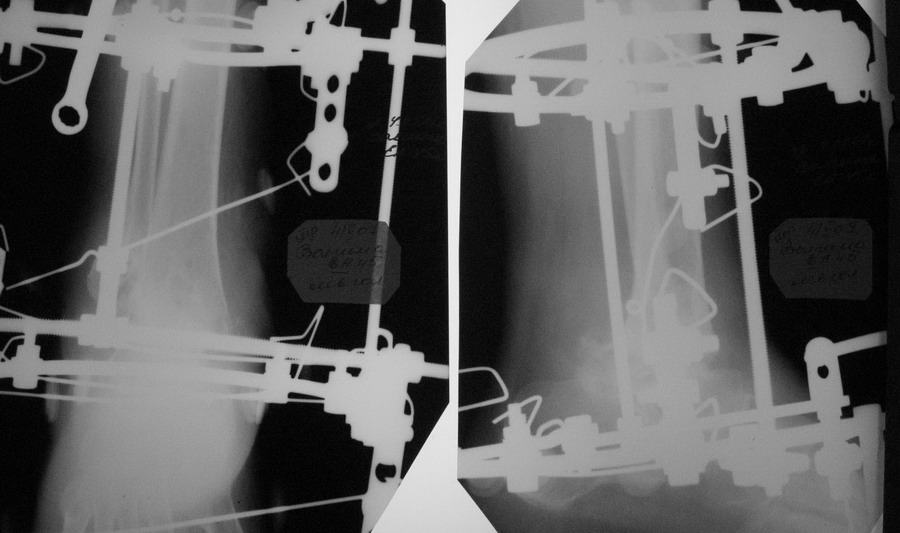

Александр Николаевич! Постарался переделать рентгенограмму  - не знаю лучше ли стало- снимки никудышные:(

Что касается подтаранного сустава, то постарался его максимально разгрузить.